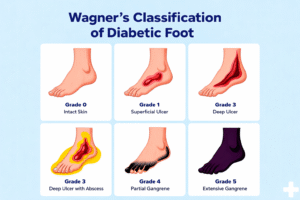

Wagner’s classification of diabetic foot is the most widely used grading system to assess the severity of diabetic foot ulcers...